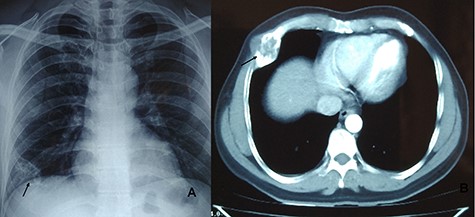

A 29-year-male presented with complain of swelling on the right posterolateral chest wall of 3-month duration associated with mild pain on and off. There was no history of trauma, and his past medical history was non-contributory. It was slowly increasing in size. His physical examination revealed a mildly tender palpable mass of tenth rib on posterolateral wall of the right chest (Fig. 5A). His all routine laboratory test results were within normal range. Chest radiograph performed showed vague lesion of right tenth rib. CT chest revealed 11 × 4 cm lytic lesion of the tenth rib involving posterolateral part (Figs 5B and C). Fine needle aspiration cytology was hemorrhagic. A right anterolateral thoracotomy was done and the mass present in posterolateral part of right 10th rib was excised (Fig. 6A). The underlying visceral pleura, lung and diaphragm were free. The mass was resected along with the adjacent parietal pleura and normal rib segment (Fig. 6B). The cut section of specimen revealed hemorrhagic material covered with thin bony shell. Histopathology confirmed the mass to be Fibrous dysplasia with aneurysmal bone cyst-like areas (Fig. 6C). His post-operative course was uneventful and discharged on 3rd post-operative day without any complaints. After 2 year of follow-up, he is doing well without any recurrence.

Mass in right posterolateral wall (A). CT chest showing lytic lesion of right tenth rib (B and C).